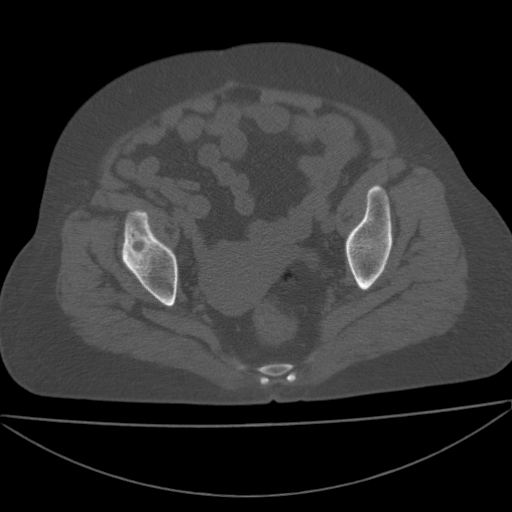

以下是引用王显瑞在2009-4-23 16:45:00的发言:[br]考虑股骨颈陈旧性骨折,股骨头缺血型坏死

以下是引用余辉在2009-4-23 17:08:00的发言:[br]考虑右髋关节退行性变.股骨颈改变考虑陈旧性骨折可能,股骨头顶部关节面下似有透亮区,股骨头皮质环增厚,考虑有股骨头坏死